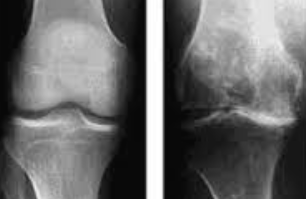

무릎 연골 손상의 주요 증상

연골 손상 정도별 증상 변화

1단계: 경미한 연골 손상 증상

연골 손상 초기 단계에서는 증상이 미미하여 단순한 피로나 근육통으로 오인하기 쉽습니다. 주요 증상으로는 운동 후 가벼운 무릎 불편감, 아침 기상 시 약간의 강직감, 날씨 변화에 따른 무릎 불편감 등이 있습니다.

이 단계에서는 일상생활에 큰 지장이 없어 대부분 간과하게 되지만, 적절한 관리가 이루어지지 않으면 손상이 진행될 수 있습니다. 따라서 가벼운 증상이라도 지속되면 전문의 상담을 받는 것이 중요합니다.

2단계: 중등도 연골 손상 증상

연골 손상이 중등도로 진행되면 증상이 더욱 뚜렷해집니다. 계단 오르내리기, 쪼그려 앉기, 장시간 걷기 등의 활동에서 명확한 통증이 나타납니다. 무릎 관절에서 소리가 자주 나며, 무릎을 완전히 구부리거나 펴는 것이 어려워집니다.

이 단계에서는 무릎 부종이 눈에 띄게 나타나며, 활동 후 무릎이 무겁고 뻣뻣한 느낌이 지속됩니다. 진통제를 복용해야 할 정도의 통증이 발생하며, 수면 중에도 무릎 때문에 잠을 깨는 경우가 생깁니다.

3단계: 심각한 연골 손상 증상

연골 손상이 심각한 단계에 이르면 일상생활에 심각한 지장을 초래합니다. 평지 보행에서도 통증이 발생하며, 무릎을 움직일 때마다 심한 통증과 함께 관절음이 지속적으로 나타납니다.

무릎 관절의 변형이 육안으로도 확인되며, 무릎이 완전히 펴지지 않거나 구부러지지 않는 관절 강직이 나타납니다. 무릎에 힘이 빠지는 느낌과 함께 관절 불안정성이 심화되어 넘어질 위험이 증가합니다.